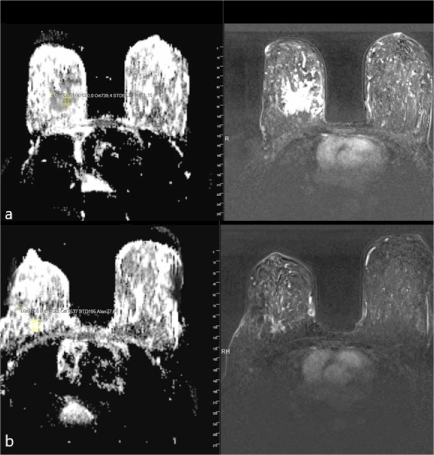

The relationship between size of the tumor after surgery and Ki-index with tumor size before NAC and ADC are shown in Table 1c (Figure 3a-b). A positive correlation was detected between tumor size after surgery and ADC value before NAC (r = 0.57; p < 0.001). No statistically significant relationship could be detected between tumor size before NAC and after surgery (p > 0.05). There was a moderate negative correlation between Ki-67 index obtained from tumor tissue after surgery and ADC value before NAC (r = -0.34; p <0.05). On the otherhand no statistically significant association could be detected between Ki-67 index and tumor size measured before NAC (p > 0.05) (Table 1c).

Figure 3a-b. ADC mapping and T1 weighted subtraction imaging of a 66-year-old case detected breast invasive ductal carcinoma with a mass of 22x16x19 mm with speculated contour; a) Mean ADC value before NAC was 0.72 and b) Mean ADC after NAC was 1.7.